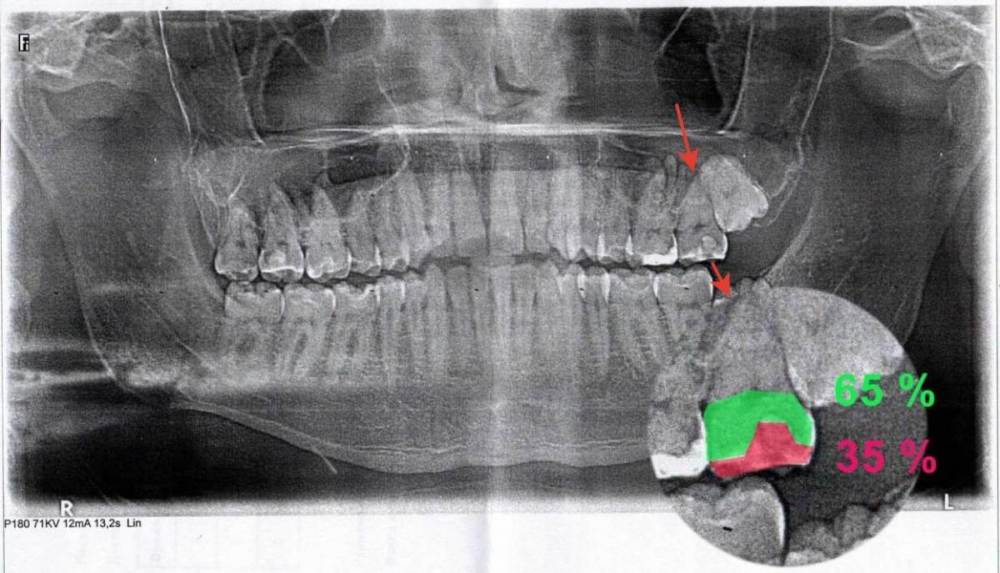

nikolas_magpies Опубликовано 14 декабря, 2023 Поделиться Опубликовано 14 декабря, 2023 Добрый день. У меня есть полис ДМС со стоматологией. В него НЕ входит лечение пораженного кариесом зуба, если он разрушен более, чем на половину (ИРОПЗ > 0,5). Появилась боль в 27 зубе. Обратился в поликлинику по ДМС. Врач стоматолог-терапевт сделал ортопантомограмму и отказал в лечение по ДМС, ссылаясь на разрушенность в 60%. Я с этим решением не согласен, по панорамному снимку видно разрушение явно меньше, чем на 50%, так как нижняя часть коронковой части зуба, которая светится белым цветом — является пломбировочным материалом, а остальная серая часть зуба до десны — является здоровым тканями зуба. Прикладываю сам снимок, подсчет площади старой пломбы и коронковой части зуба без пломбы. Подскажите, пожалуйста, как вы считаете, разрушен этот зуб более, чем на 50% или нет? Ссылка на комментарий